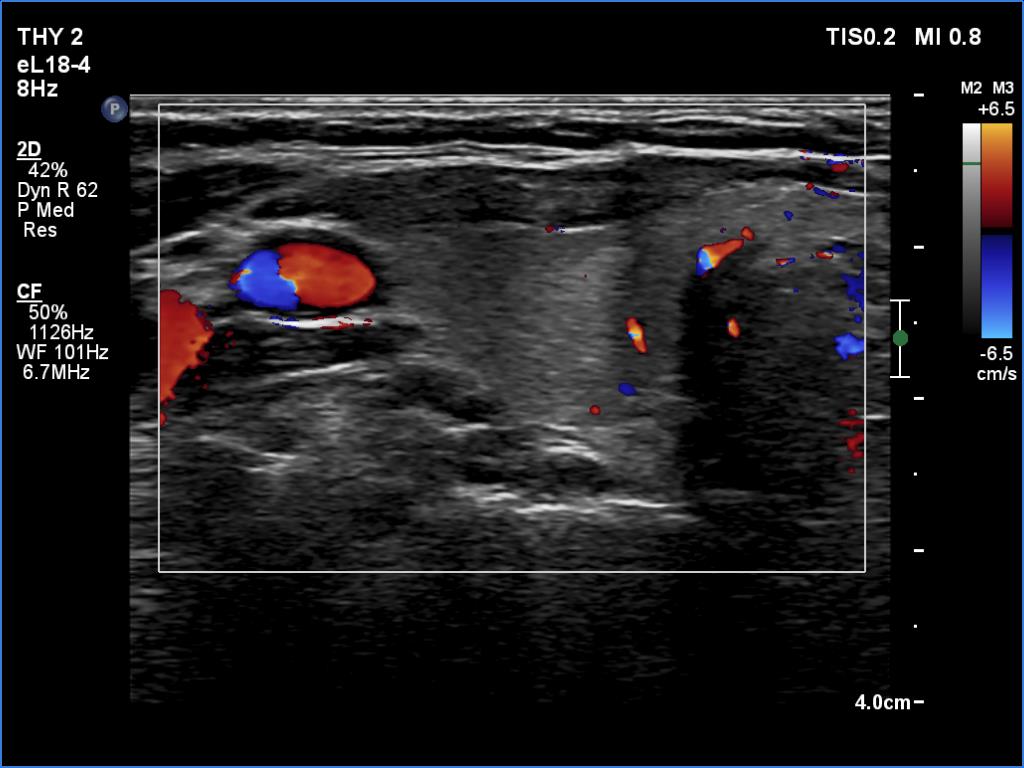

Ultrasonography: The thyroid presented with hypoechoic areas which had blurred borders. The echogenicity index was approximately 65% in the right and 20% in the left lobe. The thyroid was almost completely avascular.

Ultrasonography: The right lobe decreased in size as did the extent of hypoechogenic areas in this lobe. The left lobe remained unchanged.

Ultrasonography: The pattern of the entire thyroid became almost completely normal. Only small hypoechoic areas were observed.

Ultrasonography: The thyroid was intact.

3. A discrete hypoechoic lesion of thyroiditis frequently resembles a suspicious nodule with blurred and lobulated margins and nonparallel orientation, as happened in this case. We must be aware of the clinical data when analyzing an ultrasound pattern.